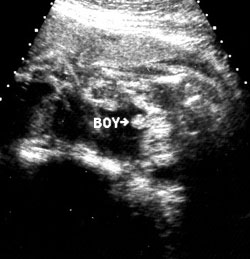

الولد

ولد في الأسبوع ال 15